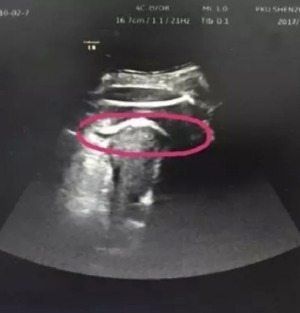

Una mujer casi fallece en China después de que el bebé que tenía en su vientre rompiera de una patada la pared del útero. Fue a revisarse al hospital Shenzen de la Universidad de Pekín, donde le hicieron una ecografía y los doctores descubrieron que las piernas del bebé salían por fuera del útero.

El médico de Zhang, Zhong Shilin, dijo que el útero de la mujer tenía una ruptura de casi 3 pulgadas de largo. El líquido amniótico de Zhang también había comenzado a fluir hacia su abdomen.